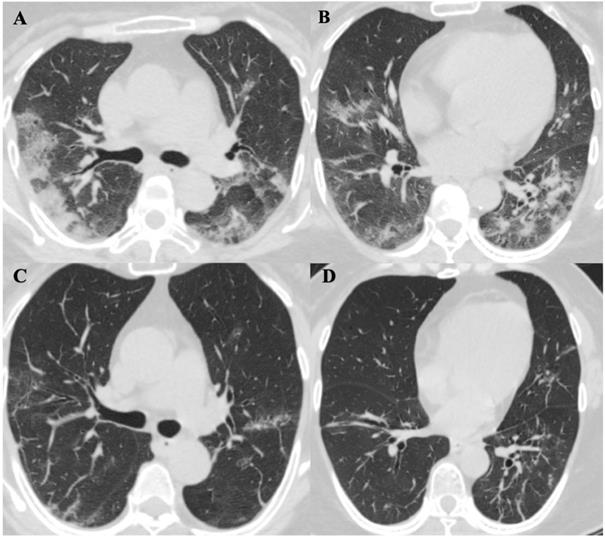

Chest computed tomography (CT) scans were performed for all patients on the day of diagnosis. Initially, six patients (60%) were noted to have a bilateral distribution of patchy shadows or ground glass opacity except in four patients (patients 2, 4, 6, and 7) (Table 4). Patients received serial CT scans in the follow up or according to clinical condition changes afterwards. Patient 2 was found to have multiple patchy ground-glass opacities in both lungs in a CT scan on day four after admission, and patient 7 presented with multiple patchy lesions in bilateral lungs day 10 after admission. In contrast, there were two patients (20%) (patients 4 and 6) who had no radiological evidence of pneumonia during hospitalization. In total, eight (80%) patients showed bilateral pneumonia (100%). No pneumothorax or pleural effusion occurred in any patient. The evolution of CT images in one patient (patient 5) is illustrated in Figure 3, which shows the serial change of lung lesions.

ChestComputed Tomographic Images of a 57-year-old patient (Patient 5) with SARS-CoV-2 pneumonia during hospitalization. A. and B. were two different levels of Chest CT images in patient 5 on day 9 of symptoms onset, it showed bilateral distribution of patchy shadows and ground glass opacity. C. and D. showed significant lesions absorption on day 21 of symptoms onset comparing to the same level images of A. and B.

About 75% of cases of COVID-19 have been reported with bilateral pneumonia [11], while bilateral pneumonia was noted in 80% of our cases. The primary findings in CT images of COVID-19 patients were as follow [7,12] : ground glass opacities (GGO), inter- or intra-lobular septal thickening, and air space consolidation. Lung abnormalities on chest CT images were reported to show the greatest severity approximately 10 days after the initial onset of symptoms while consolidation could increase up to two weeks and be gradually absorbed [12]. Fibrous stripes were recognized upon improvement in the disease course [13]. These features were mostly in line with our cases (Figure 3). Notably, a few slightly enlarged lymph nodes were found in the mediastinum in two of the 10 cases (patients 5 and 7), which the enlargement subsided in the fourth CT performed on day 21 after symptom onset in patient 5. Reactive lymphadenopathy due to infection might be one of the explanations.